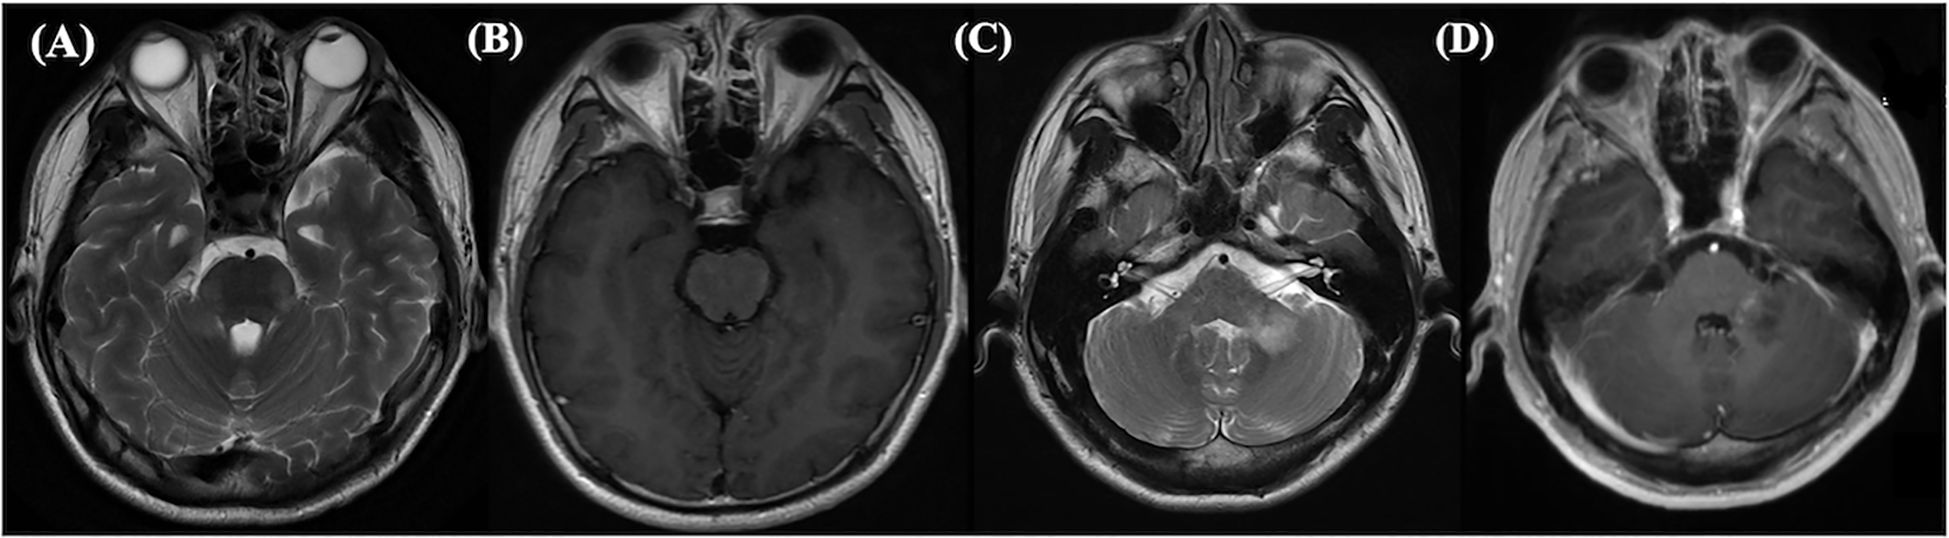

Figure 3

Eight MRI brain scans labeled A to H, showcasing different views and contrasts. The scans depict variations in brain structure and tissue contrast, highlighting different anatomical features and potential conditions. Each scan provides unique imaging details for medical analysis.

Figure 3. This abnormal MRI is from a 65-year-old male, who tested positive for double antibodies upon first admission. Long signals on T1-weighted (A) and T2-weighted (B) images, slightly high signals on DWI (C), and enhanced shadows on Gd enhancement (D) can be seen in the hippocampus. Long signals on T1-weighted (E) and T2-weighted (F) images, slightly high signals on DWI (G), and enhanced shadows on Gd enhancement (H) can be seen in the basal ganglion.

In our study, patients with positive MRI findings exhibited overlapping manifestations of MOGAD and anti-NMDARE, such as involvement of the cerebral cortex, basal ganglia, and brainstem, (Figures 2, 3), which is consistent with previous studies (5). Patients with anti-NMDARE typically show normal or mildly abnormal MRI findings, presenting as scattered cortical or subcortical T2-weighted hyperintensities, with a few cases showing inflammatory demyelinating changes involving the brainstem and white matter (14). In contrast, MOGAD involved more extensive imaging abnormalities, affecting the cortical grey matter, subcortical white matter, deep white matter, brainstem, basal ganglia, thalamus, and cerebellum, presenting as poorly demarcated hyperintensities on T2-weighted images (20, 21).It has been suggested that when anti-NMDARE patients present with positive imaging findings, especially demyelinating changes in the white matter and infratentorial regions, the presence of MNOS should be considered. The MNOS group showed a higher rate of brainstem involvement on MRI than the anti-NMDARE group. Previous research indicated that the brainstem is the most frequently involved brain structure in MNOS patients (5).